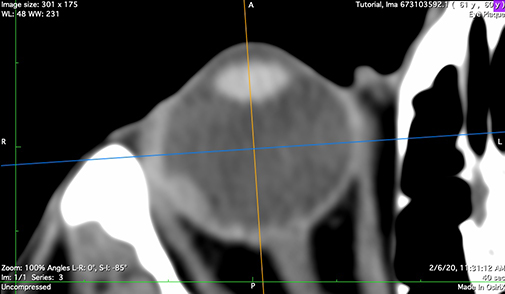

sagittal

Sagittal bisecting reconstruction. Used to verify cylindrical symmetry and anterior oblateness

n-axial

Axial bisector illustrating the nerve-coronal plane (blue axis)